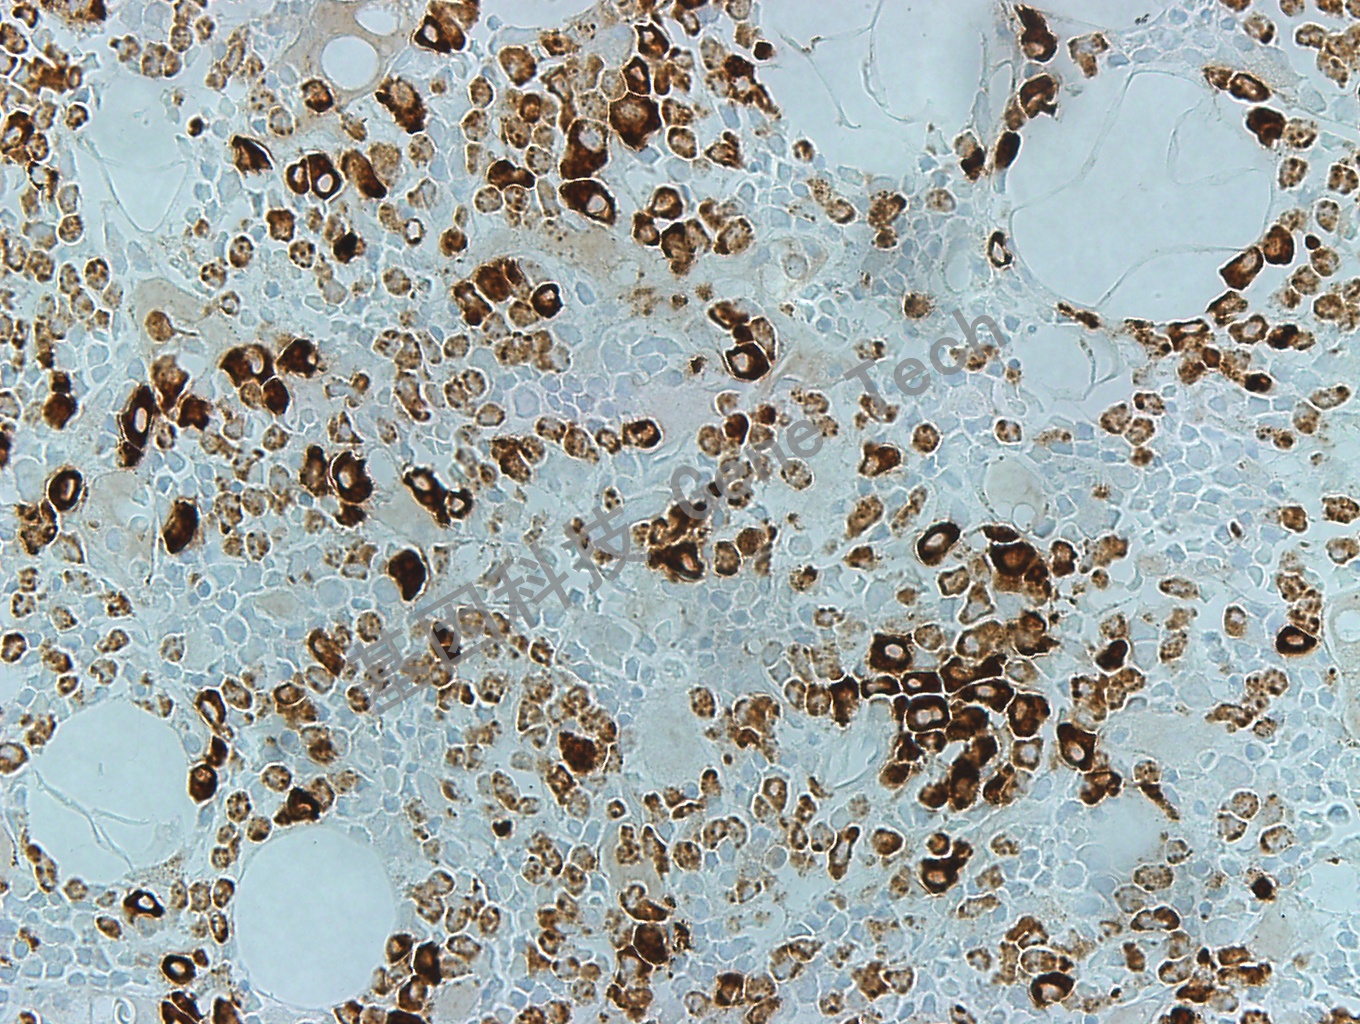

MPO GT2032 胞浆 骨髓40_副本.jpg骨髓石蜡切片,用 MPO(GT2032)染色,细胞浆阳性,DAB 显色。